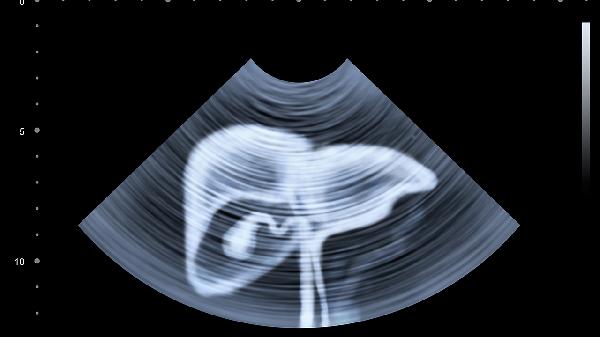

5、就医建议。若上腹部不适伴有背疼持续或加重,尤其伴随发热、呕吐、黄疸等症状,需及时就医,进行腹部超声、CT或内镜检查以明确病因。